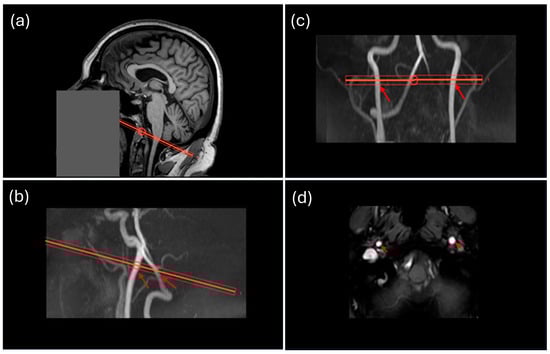

2.4. Flow Quantification from Flow MRI